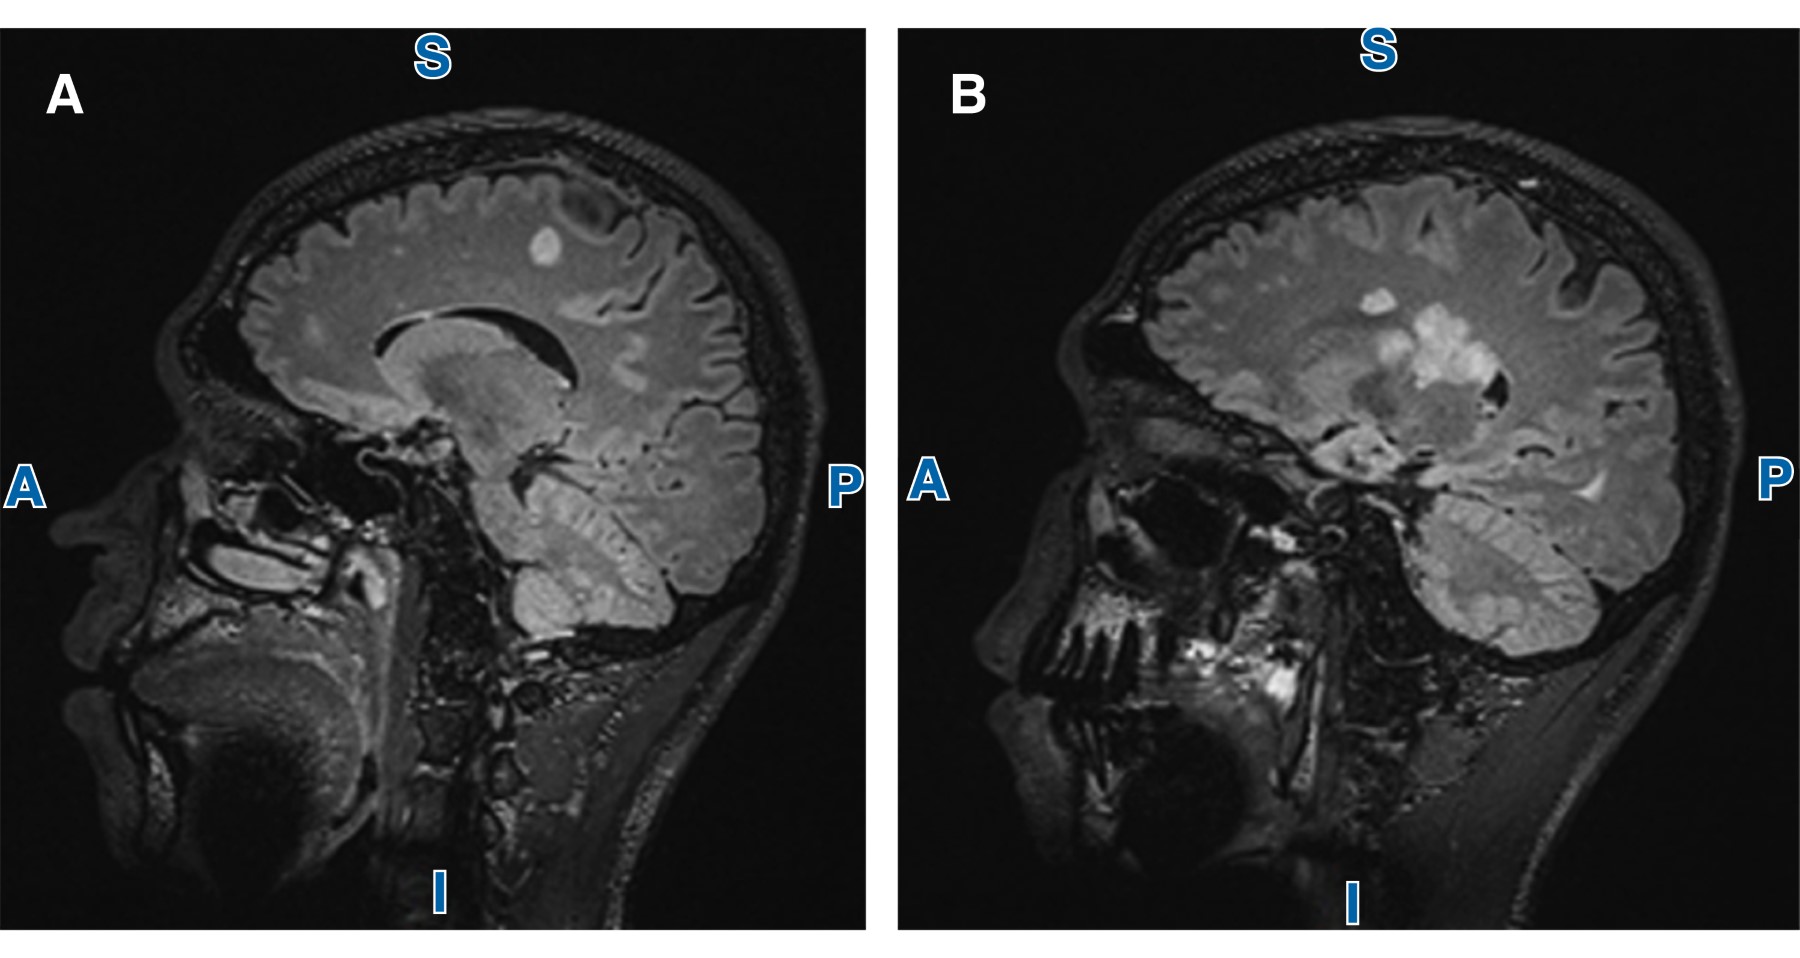

A las tres semanas del inicio de los síntomas se realizó una segunda IRM que mostró progresión de la actividad inflamatoria de forma severa, con presencia de lesiones intraaxiales ovoideas y confluentes supratentoriales e infratentoriales en cuerpo calloso a nivel de la corona radiada, en sustancia blanca periventricular a nivel frontotemporal, subcortical temporoparietal y occipital y oliva bulbar derecha, además de lesiones intramedulares (Figura 2).